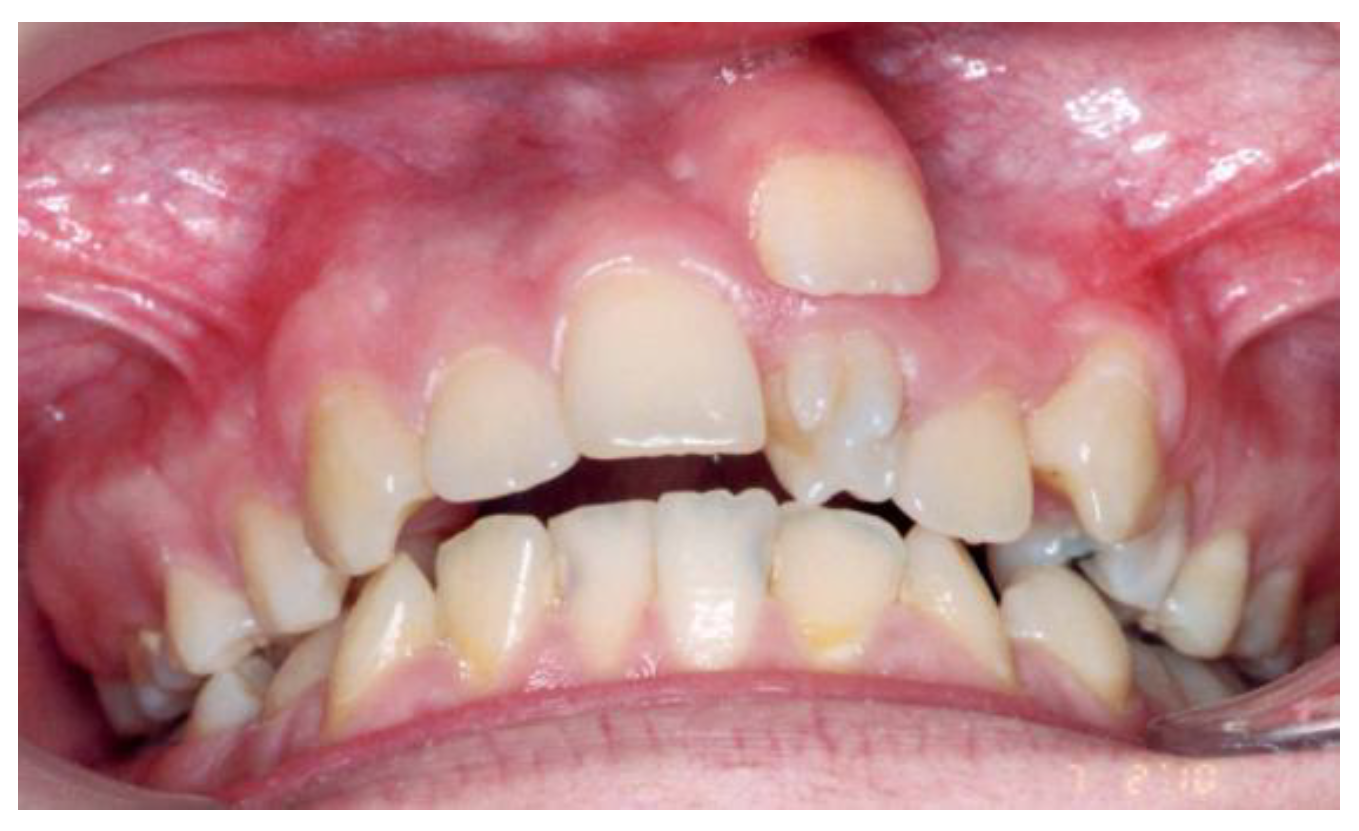

The increased frequency of ST in the maxillary incisor region (Figure 2) may be linked to intricate tissue rearrangements and morphogenetic activity in this area [2,17,20,25]. Nevertheless, no single theory fully accounts for the wide diversity of clinical presentations, suggesting that the etiology of ST is multifactorial, shaped by a complex interplay between genetic predisposition and environmental influences [3,24].

Figure 2. Supernumerary teeth located in the maxillary incisor area.